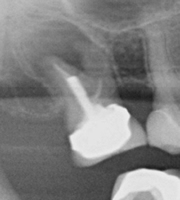

• The dentist will continue cleaning out the canals using the same process as before. Once the canals are clean and dry they will be filled with a material called ‘Gutta Percha’ which is placed into the root canal until it is sealed.

• An X-ray is then taken to check that the canals have been filled completely.

• A permanent filling will then be put in place.